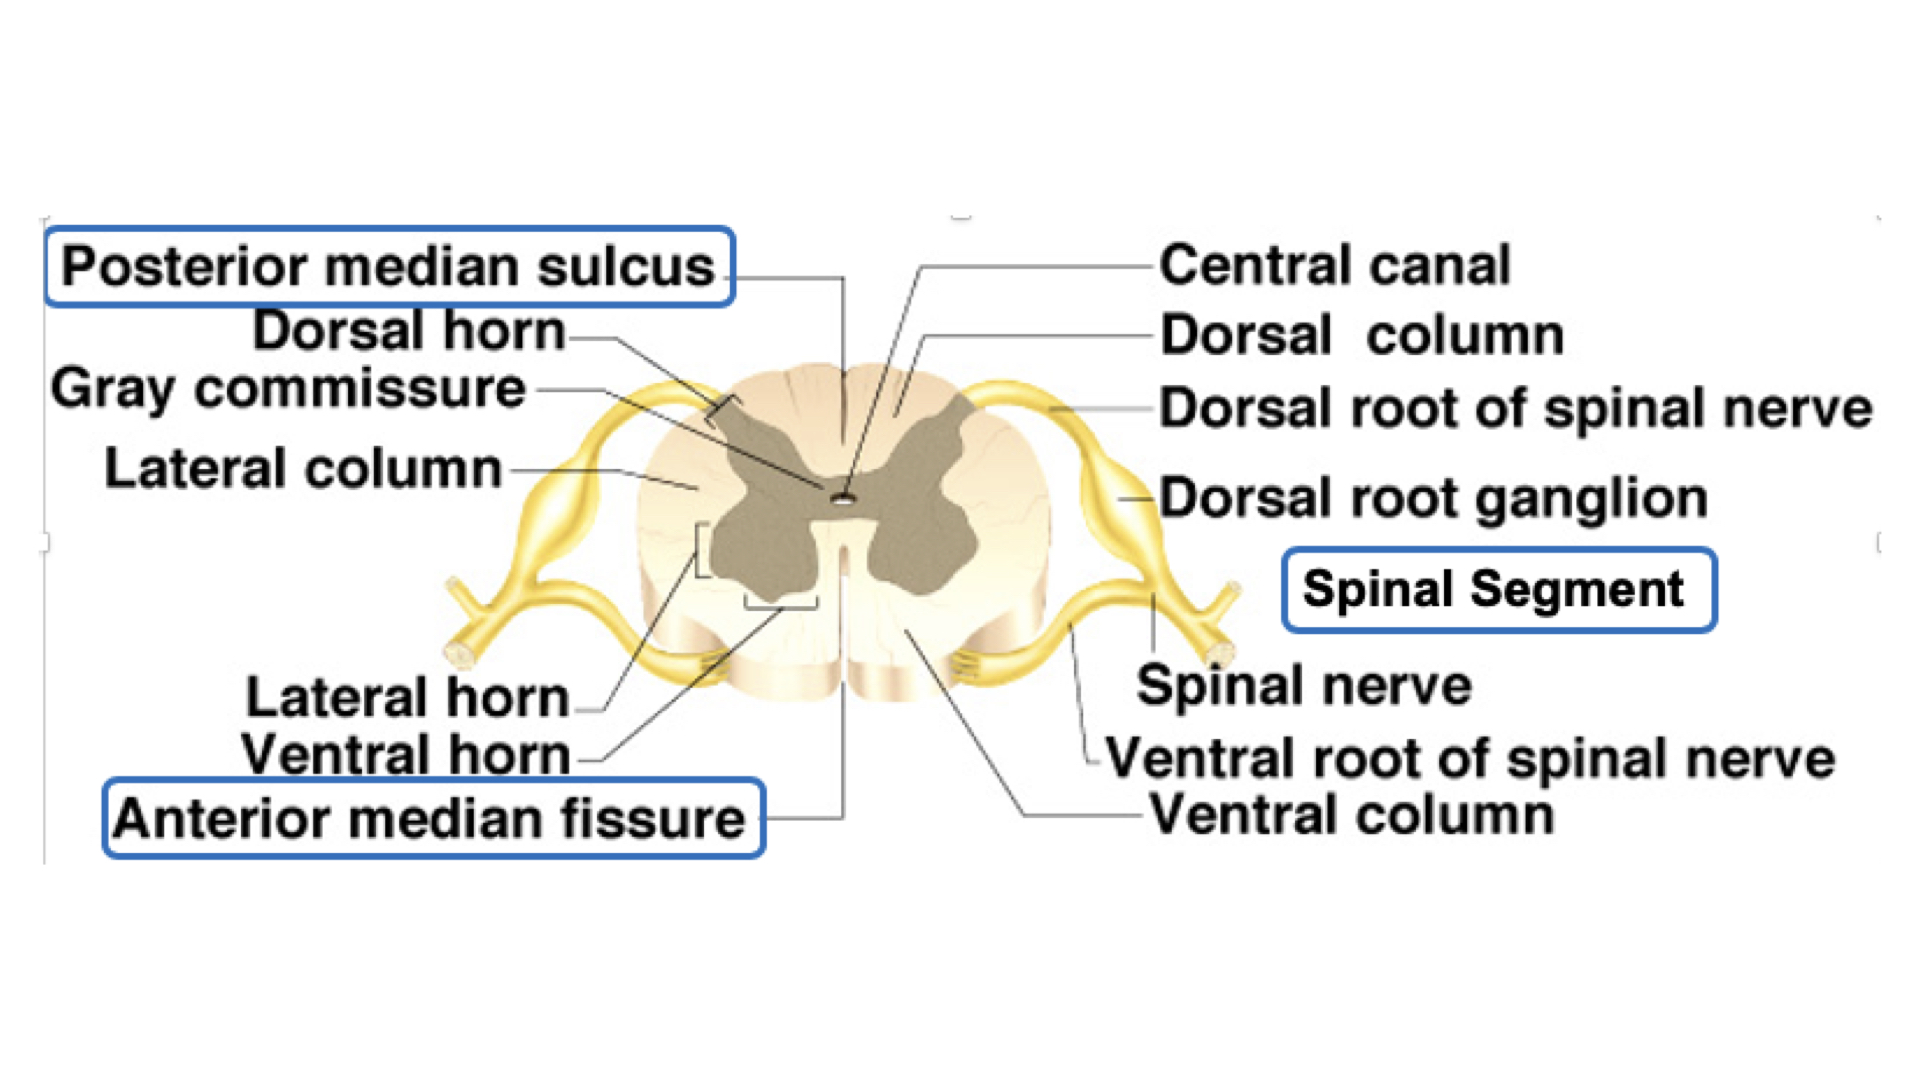

4. Composed of gray & white matter – histologically H shaped grey matter surrounded by white matter

a. Gray matter - unmyelinated tissue, mainly cell bodies, soma, nissl bodies

b. White matter - myelinated tissue, mainly axons

1. Central canal - contains cerebrospinal fluid – internal canal

4. Anterior median fissure – deep groove along the ventral surface

5. posterior median sulcus – shallow groove on the dorsal surface

6. dorsal roots – sensory, afferent fibers, dorsal root ganglion, structurally unipolar, neurons from the periphery

7. ventral roots- motor, efferent fibers, dendrites and cell bodies in ventral horns, structurally - multipolar

1. Gray matter

a. Composed of neuron cell bodies,shaped like an H or butterfly

b. Six projections called horns:

1. Two dorsal gray horns

2. Two ventral gray horns

3. Two lateral gray horns - found in thoracic lumbar

c. Transverse bar called the gray commissure

d. Central canal in center of gray commissures

2. White matter

1. Anterior median fissure

2. Posterior median sulcus